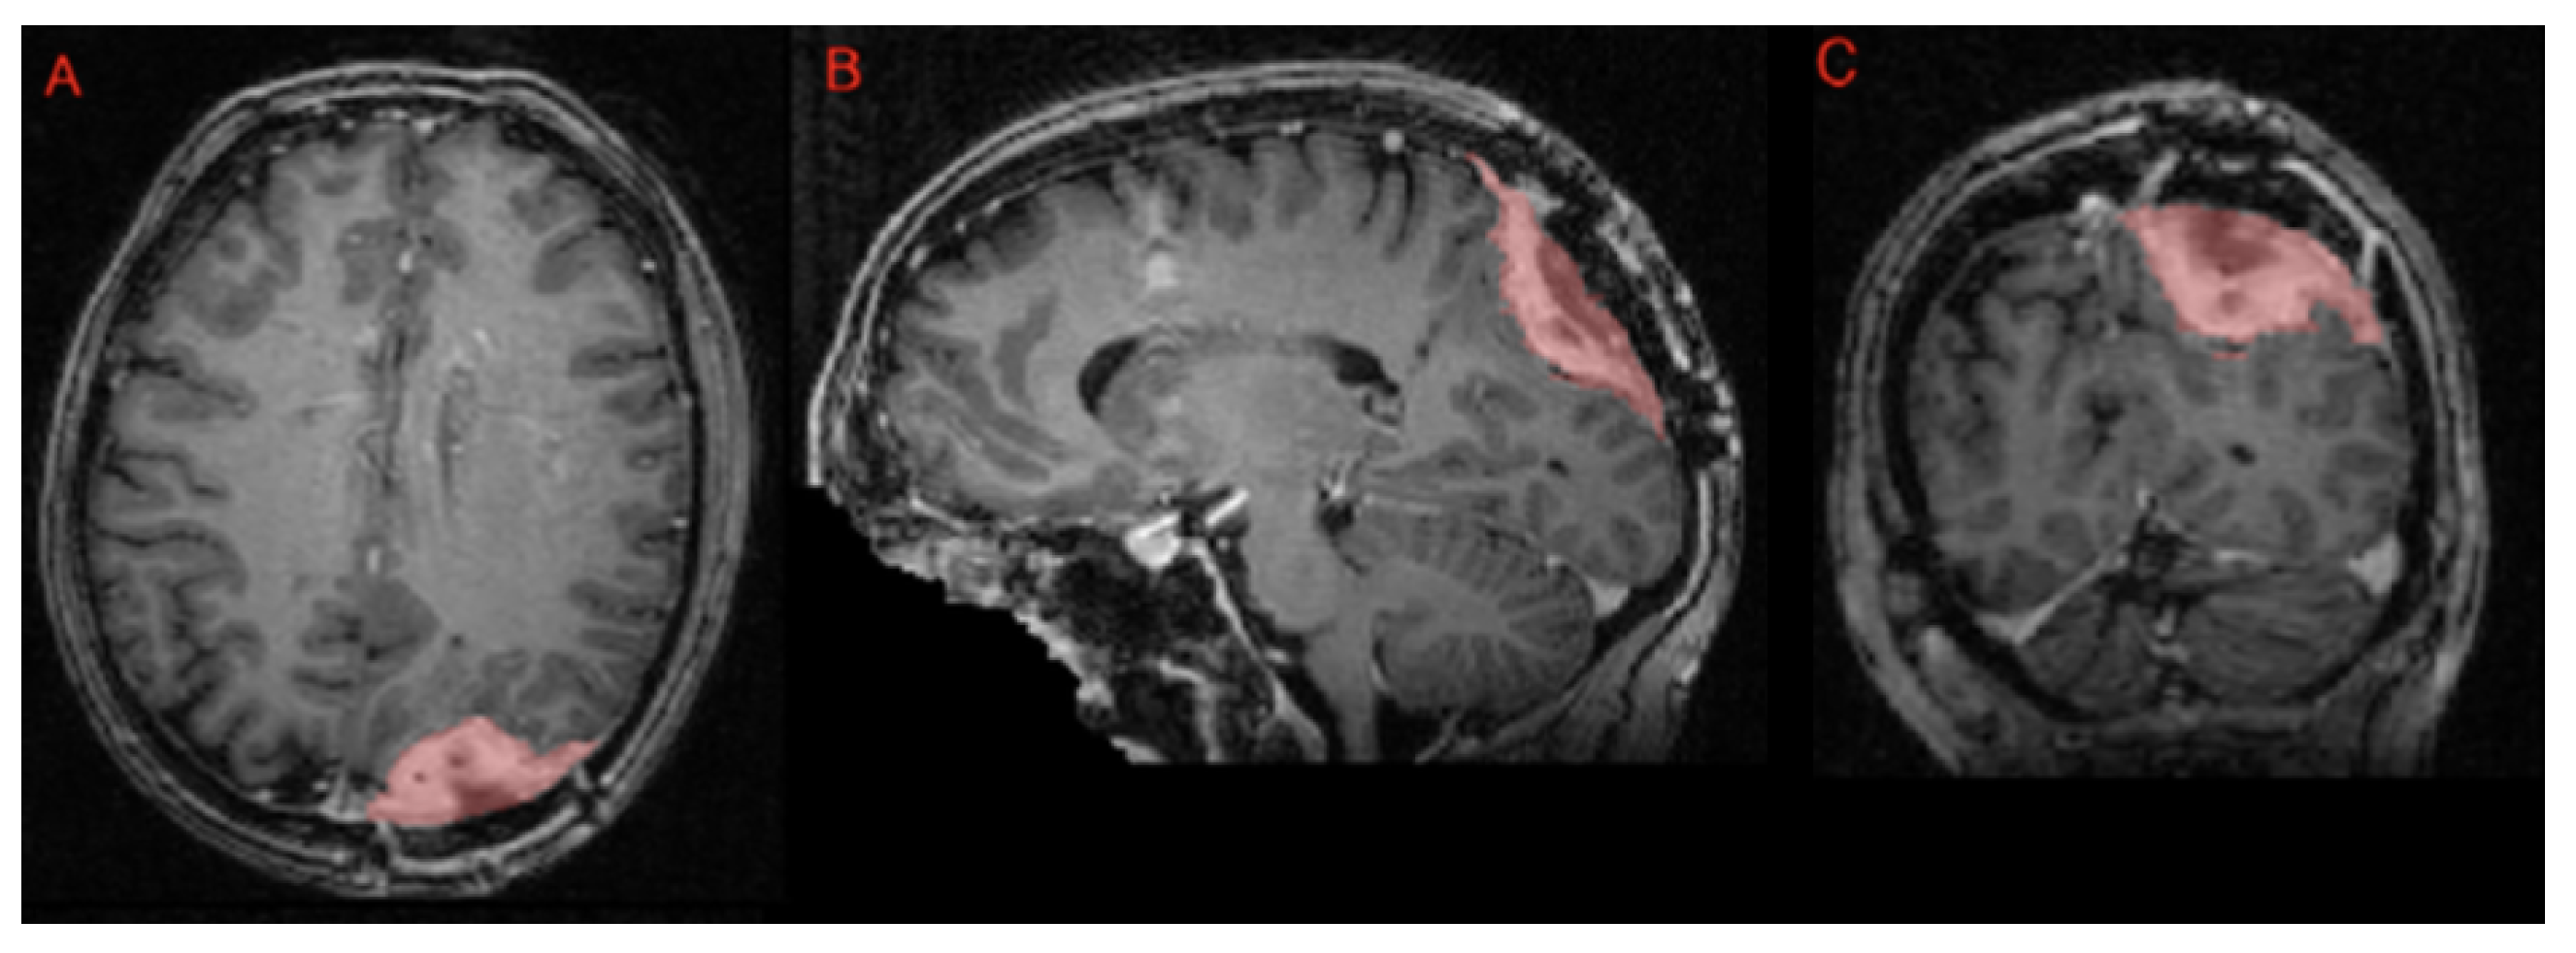

- Segmentation—meningioma: ASNR-MICCAI BraTS Intracranial Meningioma Challenge: Meningioma is the most prevalent intracranial brain tumor in adults, often causing significant health issues. While about 80% of these tumors are benign WHO grade 1 meningiomas, effectively managed through observation or therapy, the more aggressive grades 2 and 3 meningiomas pose greater risks, frequently recurring despite comprehensive treatment. Currently, there is no effective noninvasive technique for determining the grade of meningioma, its aggressiveness, or for predicting outcomes.Automated brain MRI tumor segmentation has evolved into a clinically useful tool that provides precise measurements of tumor volume, aiding in surgical and radiotherapy planning and monitoring treatment responses. Yet, most segmentation research has primarily focused on gliomas. Meningiomas present unique challenges for segmentation due to their extra-axial location and the likelihood of involving the skull base. Moreover, since meningiomas are often identified through imaging alone, accurate MRI analysis becomes crucial for effective treatment planning.The aim of the BraTS 2023 Meningioma Challenge was to develop an automated multi-compartment brain MRI segmentation algorithm specifically for meningiomas. This tool was intended not only to assist in accurate surgical and radiotherapy planning but also to pave the way for future research into meningioma classification, aggressiveness evaluation, and recurrence prediction based solely on MRI scans. For this challenge, all meningioma MRI scans were taken pre-operatively and pre-treatment. The objective was to automate the segmentation of these tumors using a three-label system: enhancing tumor (ET), non-enhancing tumor core (NETC), and surrounding non-enhancing FLAIR hyperintensity (SNFH) [10].

- Segmentation—meningioma: ASNR-MICCAI BraTS Intracranial Meningioma Challenge: Prior to manual segmentation, an automated pre-segmentation model using a deep convolutional neural network (nnU-Net) was used to produce initial multi-region segmentations. This model was initially trained on a dataset of 73 manually labeled studies from a single institution, all involving meningiomas that had undergone surgical resection. While effective, this initial training set introduced a bias that could reduce model performance for non-surgical cases. To mitigate this, the model was iteratively retrained during the challenge preparation phase using additional manually corrected cases from various sites, including non-surgical meningiomas. This iterative process aimed to enhance the model’s generalizability across diverse MRI appearances and reduce pre-segmentation bias.Manual corrections of the pre-segmented labels were performed by a diverse group of annotators, ranging from medical students to experienced neuroradiologists with over 10 years of expertise. Corrections were carried out using ITK-SNAP, an open-source tool for segmenting 3D and 4D biomedical images. Annotators were provided with detailed instructions, written descriptions of tumor sub-compartment compositions, and examples of common pre-segmentation errors to ensure consistency and reduce variability in corrections. After annotators completed their corrections, each case was reviewed by a trained neuroradiologist. Cases identified as incomplete or inaccurate were returned for additional refinement by a different annotator.For BraTS 2023 Meningioma, the task was to automatically segment intracranial meningiomas using a three-label system: enhancing tumor (ET), non-enhancing tumor core (NETC), and surrounding non-enhancing FLAIR hyperintensity (SNFH). For additional details on the pre-segmentation and annotation procedures, refer to the task manuscript: [30].

- Segmentation—meningioma radiotherapy: BraTS Meningioma Radiotherapy Challenge: Meningioma is the most common primary intracranial tumor, with about 80% being benign and effectively managed with positive outcomes. However, higher-grade meningiomas (WHO grades 2 and 3) pose greater health risks and have higher recurrence rates. They are primarily treated with radiation therapy, which may be used as the main treatment, as a postoperative adjunct, or for recurring cases. Accurate segmentation of the gross tumor volume (GTV) is critical for radiotherapy planning but remains complex and time-intensive, with no reliable automated solutions currently available.The BraTS 2024 Meningioma Radiotherapy Segmentation Challenge aimed to bridge existing gaps by developing algorithms capable of automatically segmenting gross tumor volumes (GTVs) in cranial and facial meningiomas from radiotherapy planning MRI scans.The BraTS-MEN-RT challenge exclusively includes radiotherapy planning brain MRI scans, either preoperative or postoperative, with tumors that are radiographically or pathologically consistent with meningioma. These scans consist of a single series (T1-weighted imaging) in native acquisition space, reflecting typical radiotherapy planning scenarios. This approach replaces the multi-sequence, co-registered MRI scans used in each of the BraTS 2023 automated segmentation challenges [11].

- Segmentation—meningioma radiotherapy: BraTS Meningioma Radiotherapy Challenge: For the BraTS-MEN-RT 2024 challenge, a single “target volume” label was employed, representing both the gross tumor volume (GTV) and any at-risk postoperative site. Consequently, the definition of GTV varies depending on the radiotherapy planning context:

- Preoperative setting: The target volume includes the portion of the tumor visible on T1c brain MRI.

- Postoperative setting: The target volume includes the resection bed and any residual enhancing tumor (ET) visible on T1c brain MRI.

Figure 12 provides an example of postoperative meningioma data with this target volume label, illustrating how the resection bed and any residual enhancing tumor are encompassed within the single “target volume” annotation.For cases without gross tumor volume (GTV) labels provided by the treating institution (about 10% of the dataset), an automated pre-segmentation algorithm using nnU-Net was applied. All cases, whether pre-segmented or labeled by the institution, underwent manual review and correction by a senior radiation oncology resident. Subsequently, a fellowship-trained neuroradiologist (“approver”) performed a final review to ensure data quality. Manual reviews and corrections were conducted using ITKSnap [33]. - Segmentation—brain metastases: ASNR-MICCAI BraTS Brain Metastasis Challenge: The dataset includes retrospective treatment-naive brain metastasis MRI scans, adhering to the BraTS 2023 annotation protocol.The post-treatment brain metastasis MRI scans, sourced from an external dataset, are expected to follow a five-label system that includes the necrotic core of tumor (NCR), FLAIR hyperintensity (SNFH), enhancing tumor (ET), hemorrhage (HM), and resection cavity (RC). While the detailed annotation protocol for the post-treatment cases has not yet been released, additional information will be provided in the forthcoming challenge manuscript, with updates available on the official challenge website (Synapse.org) [11].